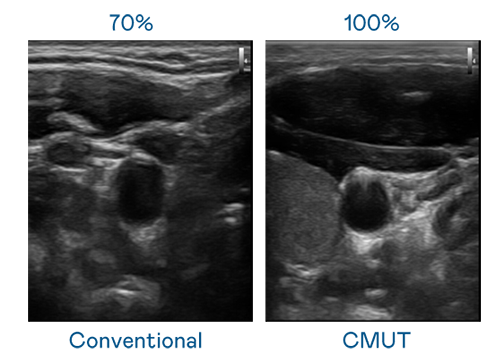

CMUT 技术是一种用电容式微机电元件来产生超音波讯号的技术。与传统 PZT 压电式技术相比,CMUT 频宽增加 30%,更宽频的超音波讯号让影像解析度大幅提升,是实现高影像品质医疗超音波扫描、促进精准医疗发展的关键技术。

大频宽带来超清晰影像

超音波影像的解析度高低,首先取决于探头能发出的讯号频宽。至尊国际 CMUT 可提供高清晰的超音波讯号,提供高频宽、高灵敏度、影像纹理细节更高的超音波影像,协助医护人员缩短影像判读时间及利用精准的医疗影像进行诊断。